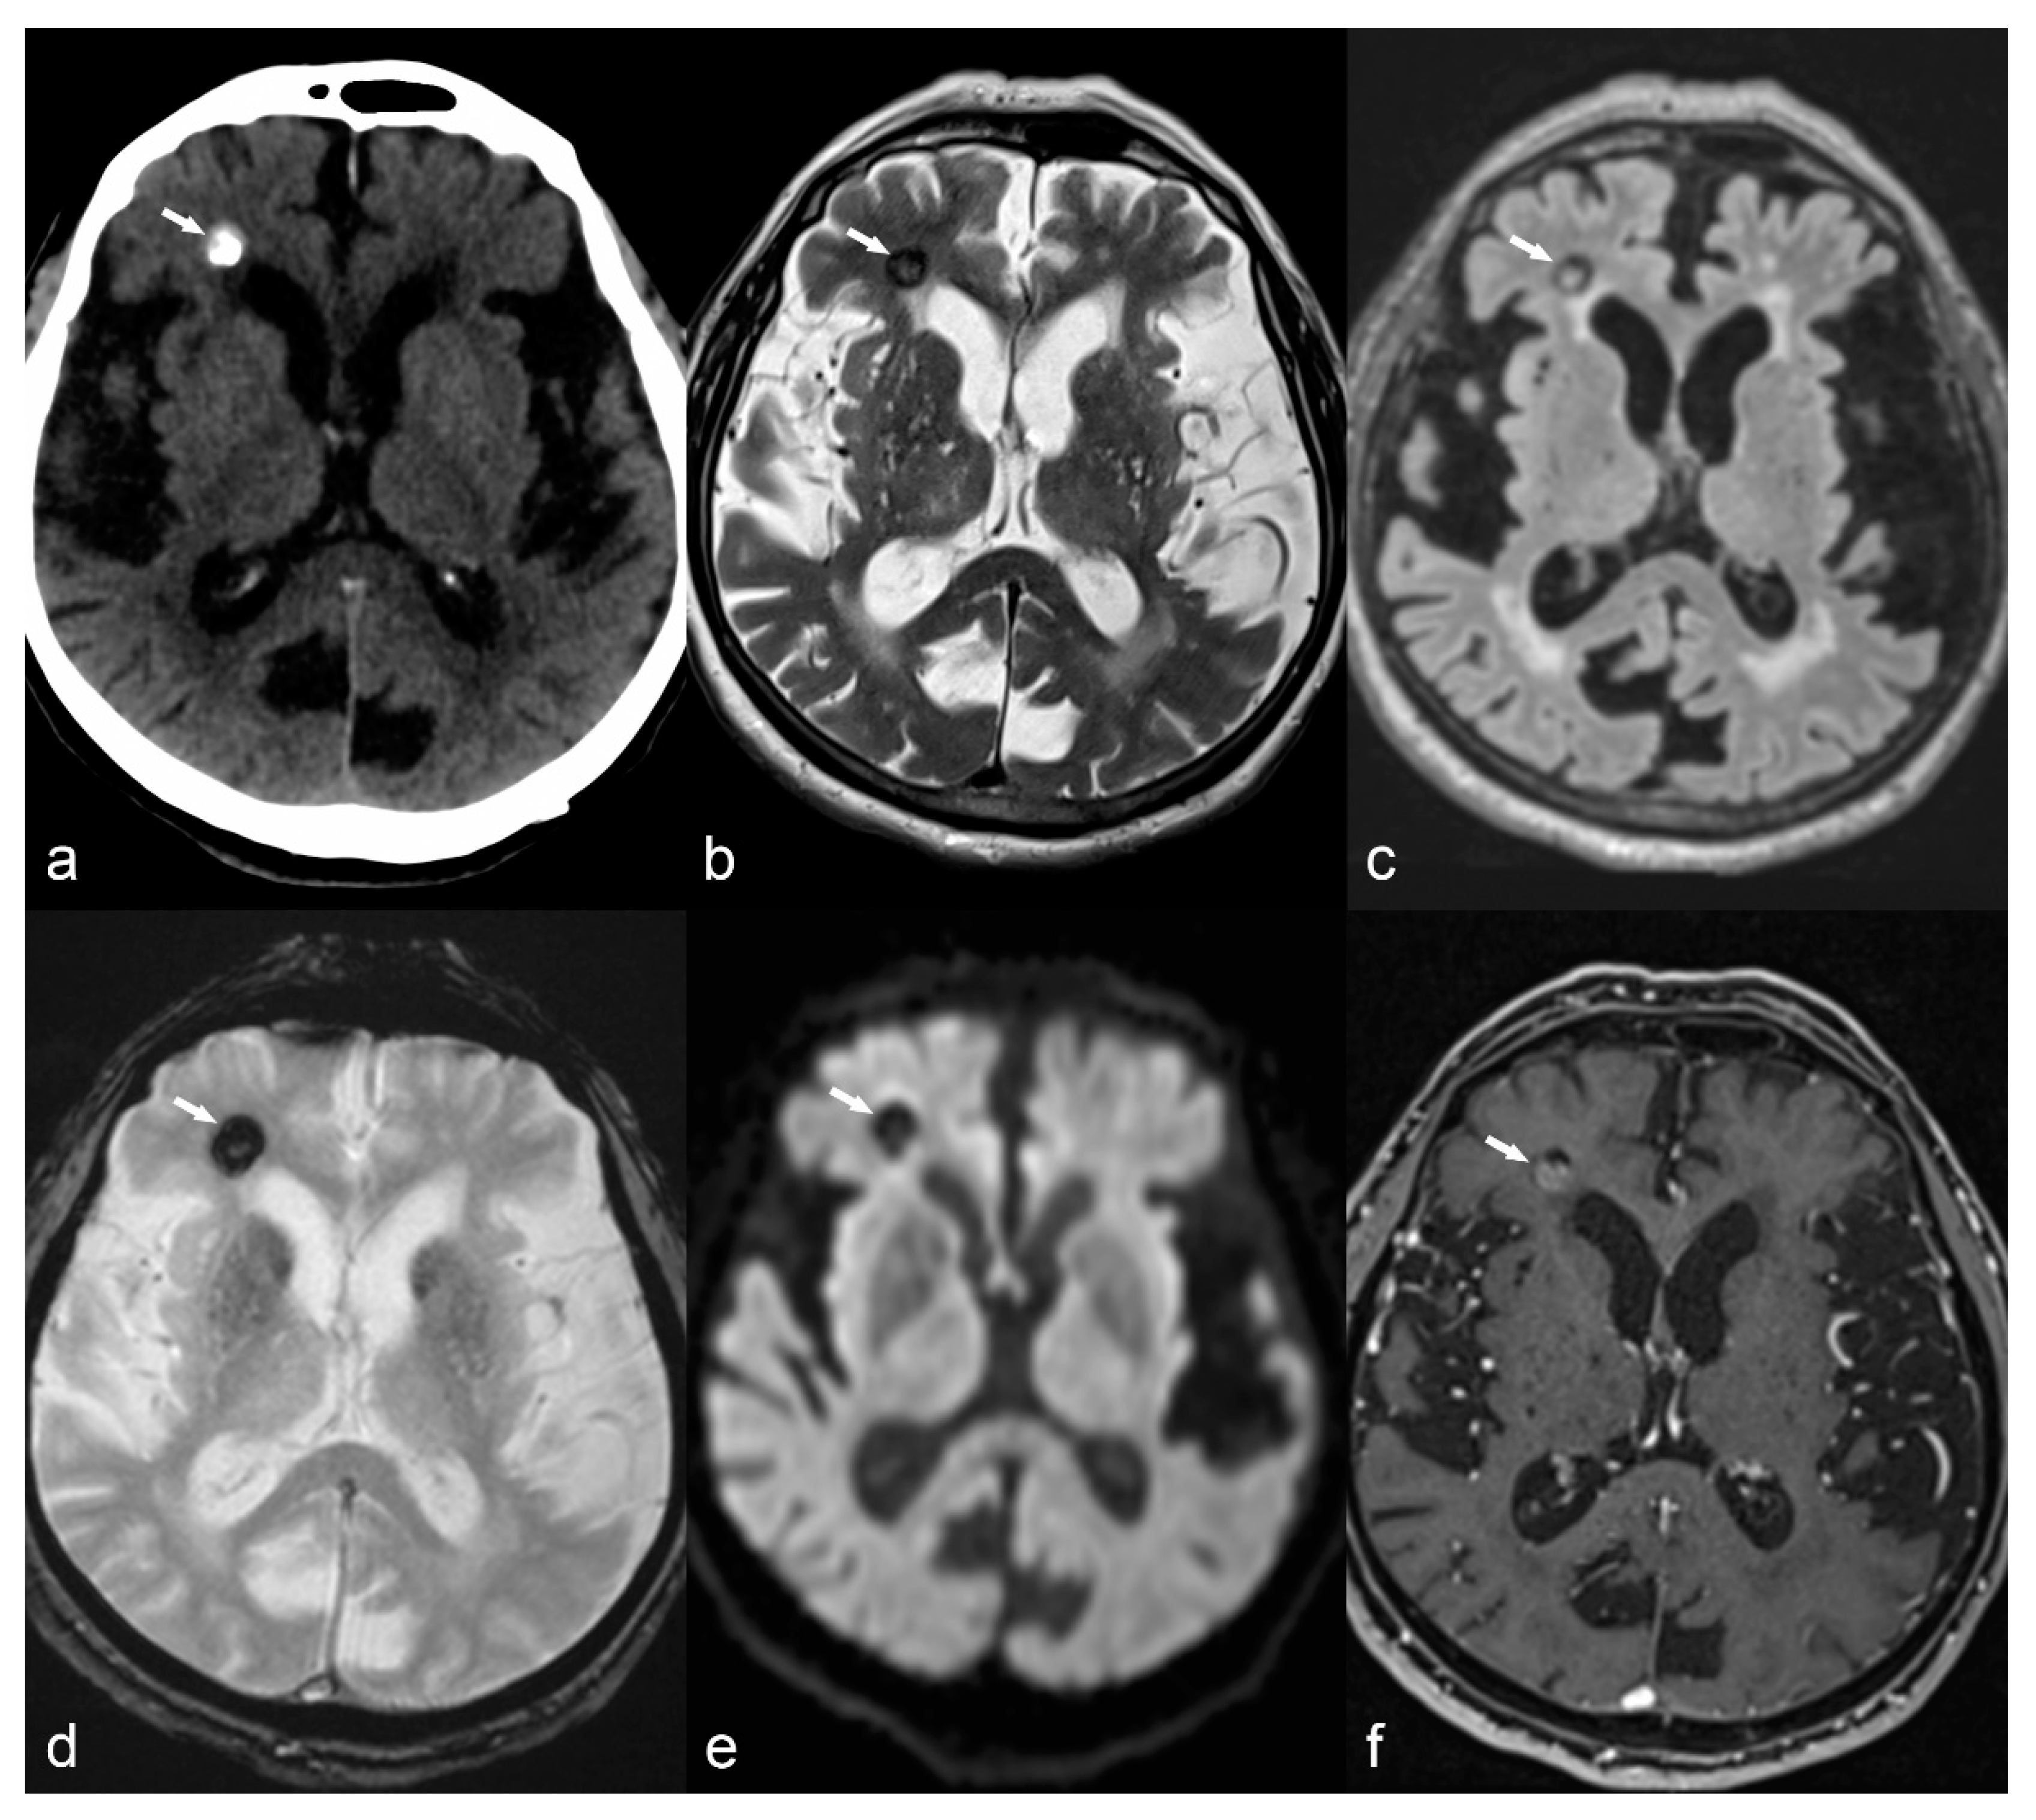

There are two types of vascular malformations associated with epilepsy: cerebral cavernous malformations, or cavernomas, and arteriovenous malformations (AVM). Cavernomas represent conglomerates of abnormal vessels with a propensity for recurrent low-grade hemorrhage. Characteristic MRI findings include typical “salt and pepper” appearance on T2WI, hypointense ring on T1 or T2 images due to hemosiderin deposition, “blooming artifact” on SWI sequence and calcification seen as a low signal on MRI and high attenuation on CT (Figure 9). Arteriovenous malformations can cause epilepsy either by a direct effect to the cortex or secondary to hemosiderosis as a consequence of previous bleeding. The characteristic serpiginous appearance of dilated vessels with a nidus and often associated intranidal aneurysms is well demonstrated after contrast enhancement on CT angiography or on MR angiography with or without contrast administration. Conventional angiography still remains the method of choice for the diagnosis of AVM and may also be used as part of its treatment. Cavernomas usually present between 40–60 years of age but in some cases, they may present in childhood between 1–3 years of age [69]. AVM have a peak presentation in the 3rd to 5th decade of life, but in 25% they may present before the age of 15 between 1–3 years of age [69].

Figure 9.

Right frontal cavernoma. Axial CT image (a) shows right frontal periventricular hyperdensity (arrow) abutting the frontal horn of the lateral ventricle. Axial T2 (b), FLAIR (c), GRE (d) and DWI (e) trace images (b = 1000) show peripheral hypointense rim with central hyperintensity (arrow). Axial T1 VIBE post-contrast image (f) shows mild enhancement (arrow) consistent with cavernoma.